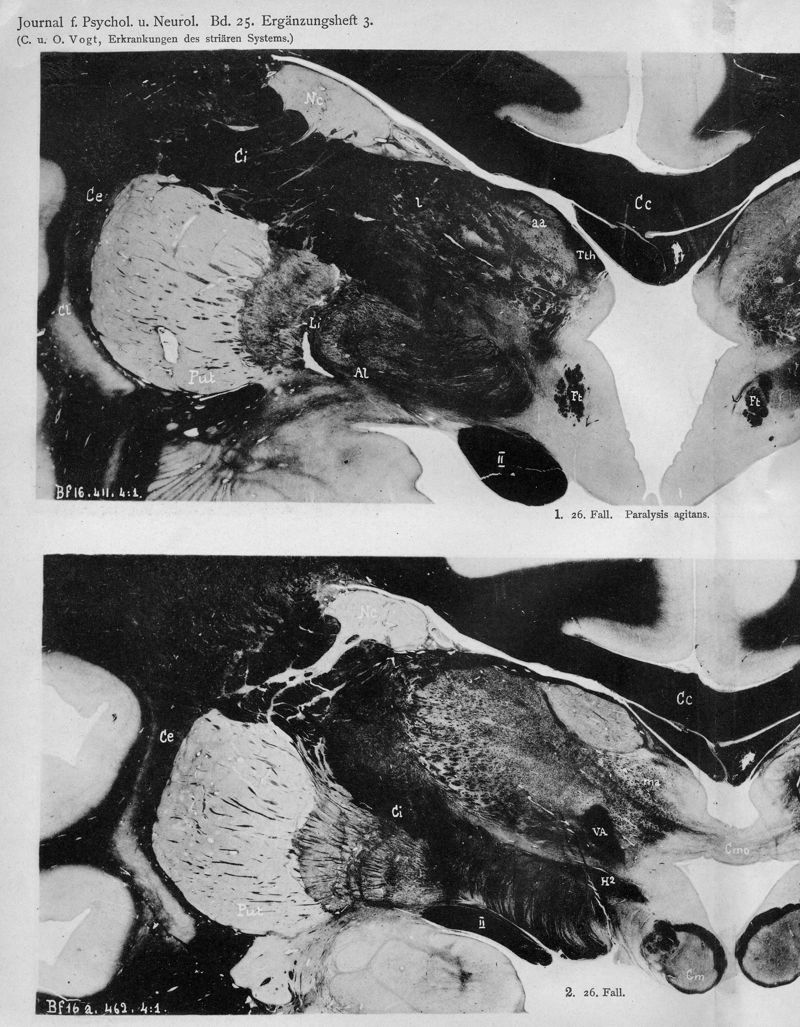

VOGT, Cécile / VOGT, O.

In : Journal für Psychologie und Neurologie,

1920, Vol. 25, pp. 627-846